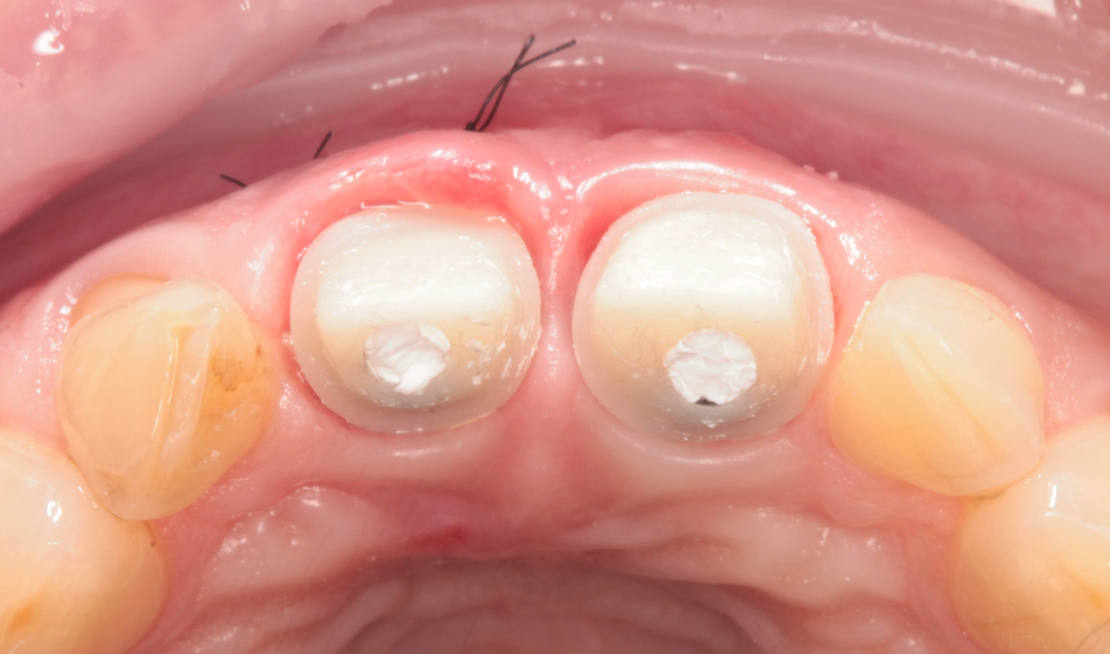

Jediným riešením bola extrakcia obidvoch zubov. Najväčšou obavou zo strany pacientky bola strata obidvoch predných zubov a následného fungovania bez nich pri práci s ľuďmi. Ideálnym riešením teda bola náhrada zubov implantátmi spolu s nasadením koruniek, a to počas jedného sedenia. V deň konzultácie bol pacientke urobený sken pomocou intraorálneho skeneru 3Shape TRIOS, ktorý nám umožňuje zobraziť 3D simuláciu ústnej dutiny. Pomocou softwaru 3Shape Implant Studio sme spojili dáta z intraorálneho skenu a CBCT, STL a DICOM súbory. V ďalšom kroku sme virtuálne vložili implantáty v správnej protetickej polohe, navrhli šablónu pre ich zavedenie, namodelovali individuálne abutmenty a korunky (obr. 4). Kompletné dáta sme exportovali pre frézovanie a 3D tlač. V laboratóriu sa pomocou 3D tlačiarne vytlačila chirurgická šablóna, ktorá nám slúži na presné zavedenie implantátov – použili sme implantačný systém Dentium Super Line. Následne boli vyfrézované zirkonové abutmenty a plastové dočasné korunky(obr. 5).

Následne sme použili protokol vŕtania a zavedenia implantátov cez šablónu (obr. 7, 8), na ktorej sme mali orientačné body pre správne napolohovanie implantátov, abutmentov a koruniek (obr. 9–14).